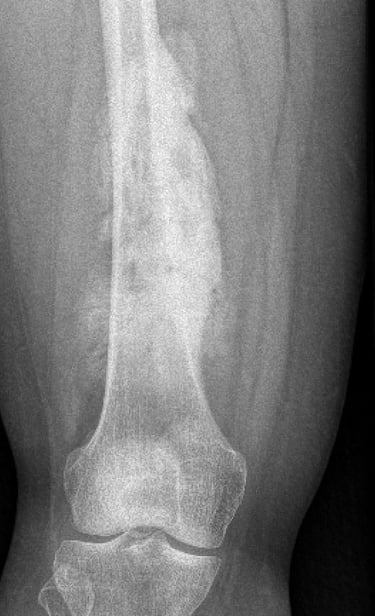

Osteosarcoma is the most common between the ages of 10 to 30 and those > 60 years old. There is no known cause in majority of patients but certain factors are known to increase your risk eg. previous radiotherapy, paget's disease, fibrous dysplasia, bone infarcts or Li Fraumeni syndrome. Most occur around the knee but can occur in any bone. Treatment generally involves combination of chemotherapy and surgery.

Diagnosis of this is generally made with Xrays, CT, MRI, PET scans and a core needle biopsy.